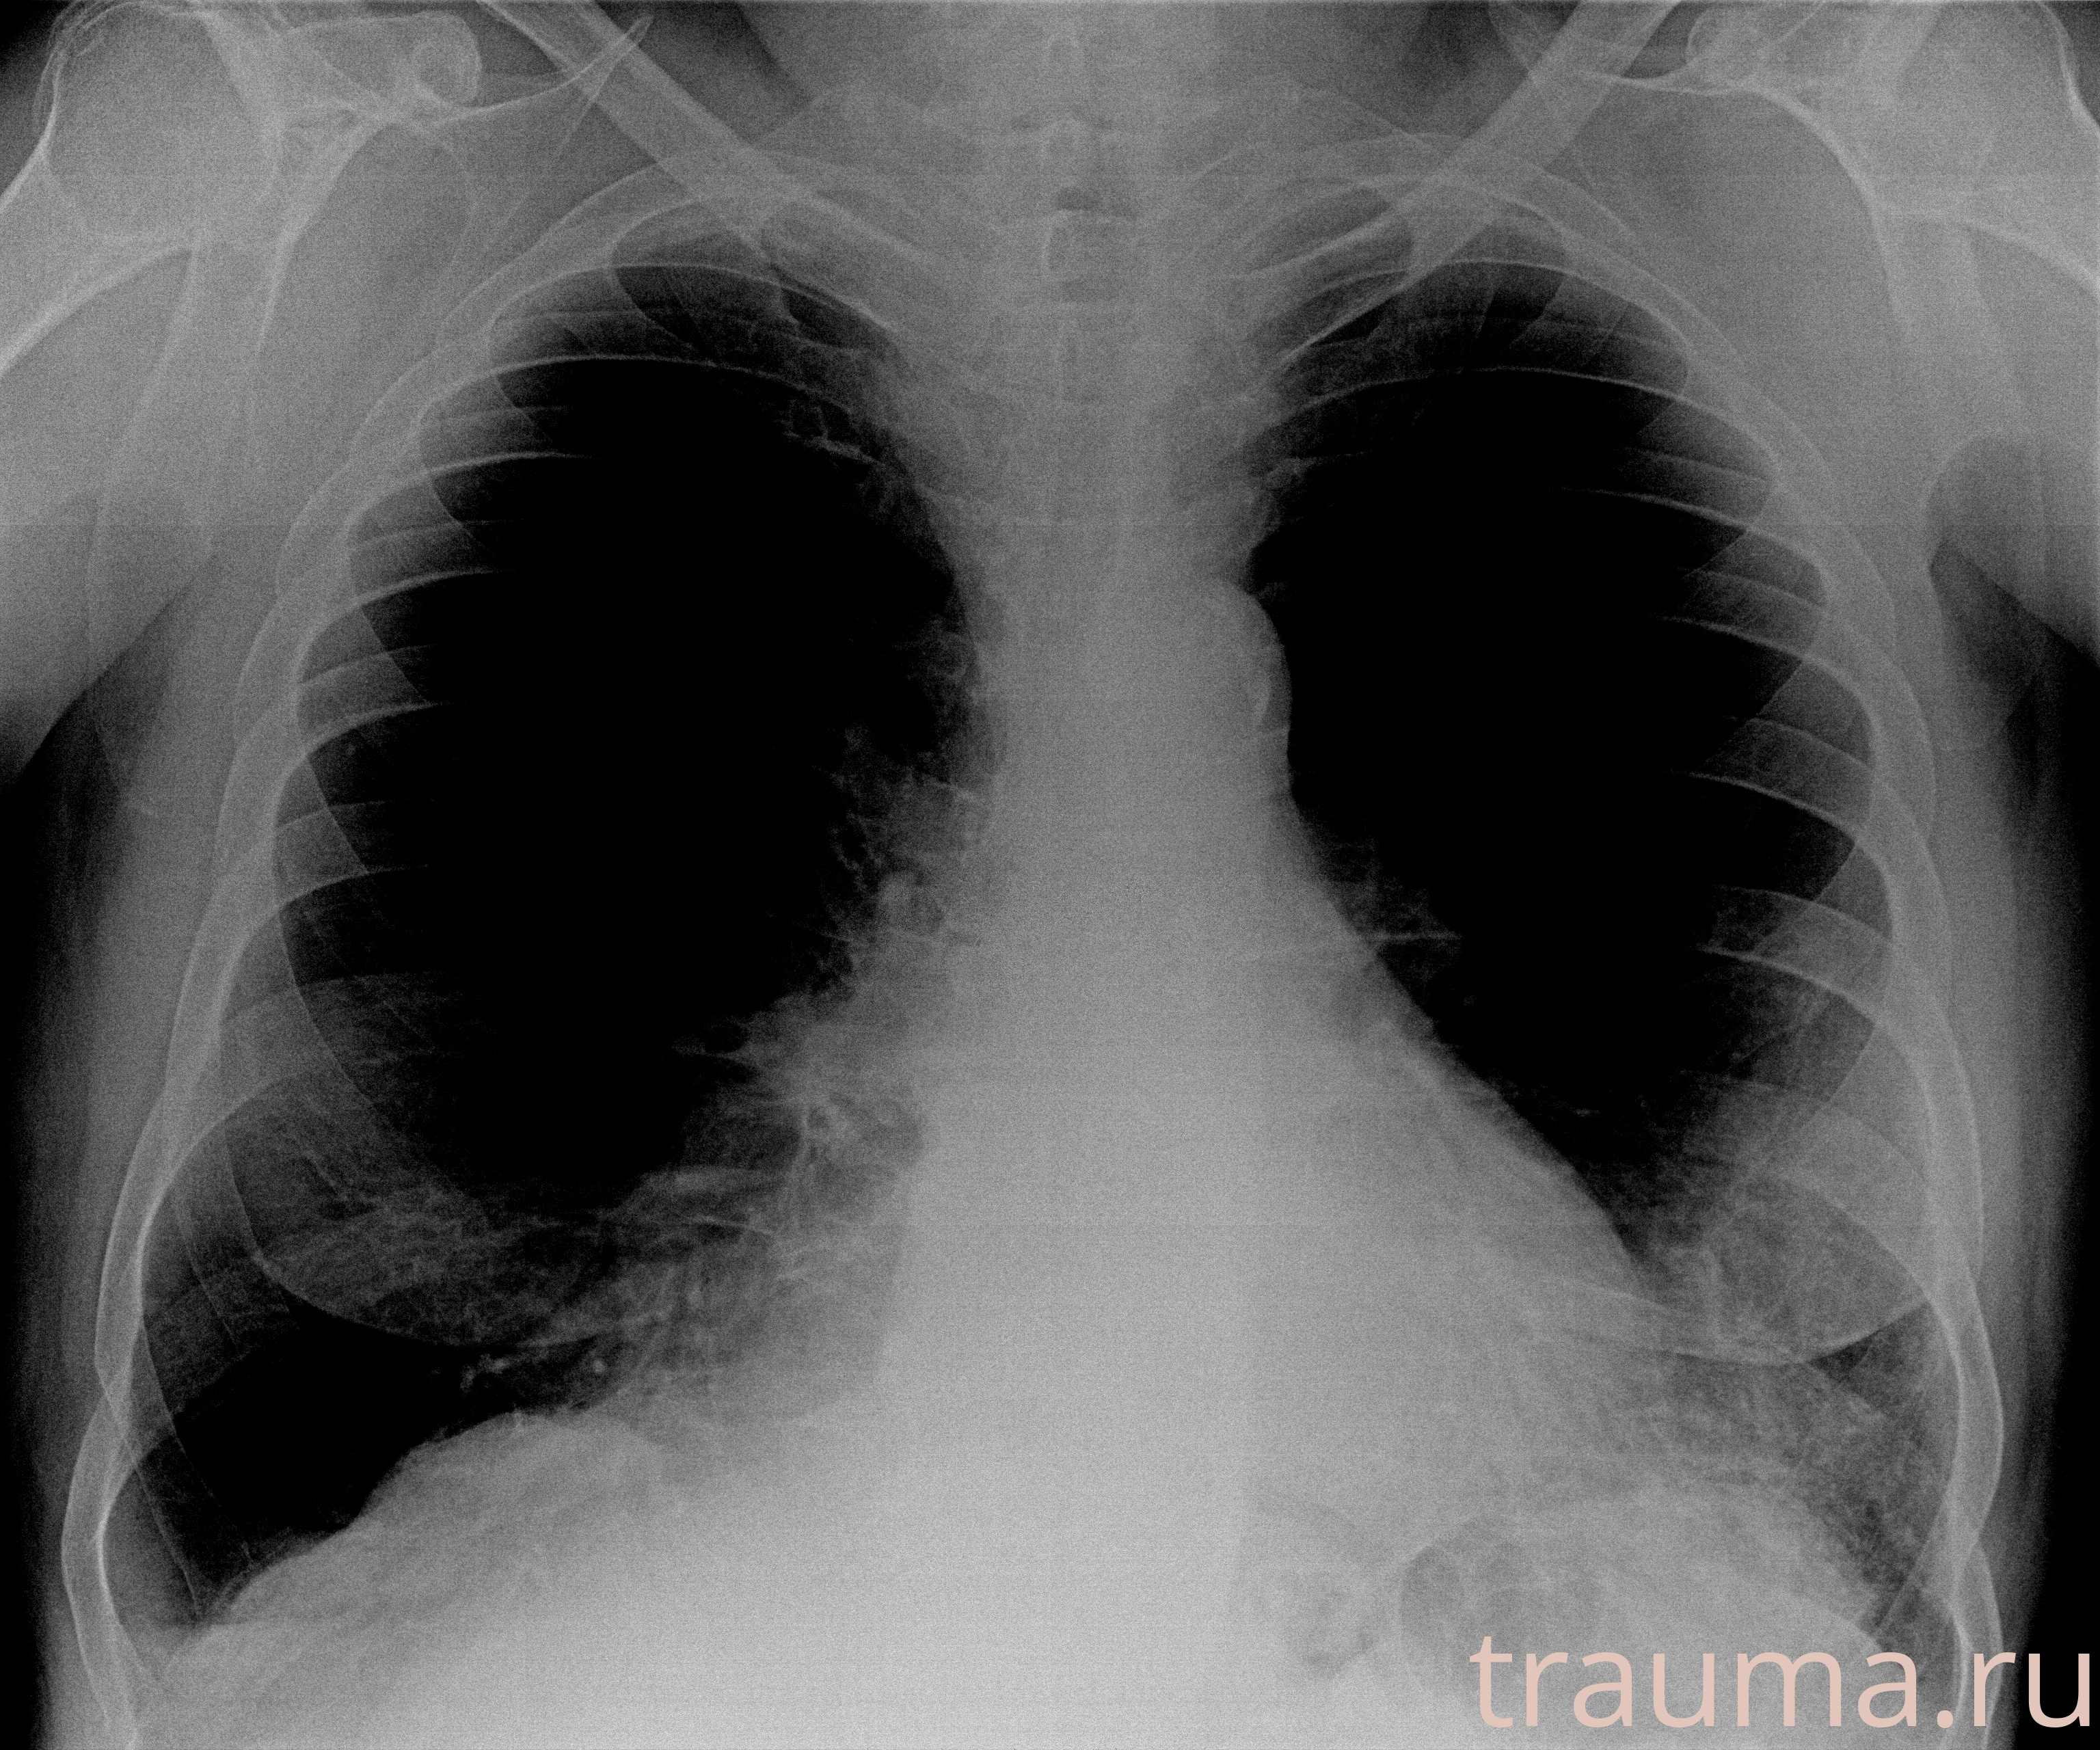

Рентгенограммы

Рентген на дому: по вашему адресу приезжает врач-рентгенолог, травматолог-ортопед с мобильным рентгеновским аппаратом, проводит диагностику травмы или заболевания, делает необходимые рентгенограммы, дает рекомендации по дальнейшему лечению. Получить качественные снимки в домашних условиях возможно благодаря уникальной методике, разработанной МосРентген Центром для института  Склифосовского

при переломе шейки бедра и пневмонии от компании МосРентген Центр - партнера Института имени Склифосовского